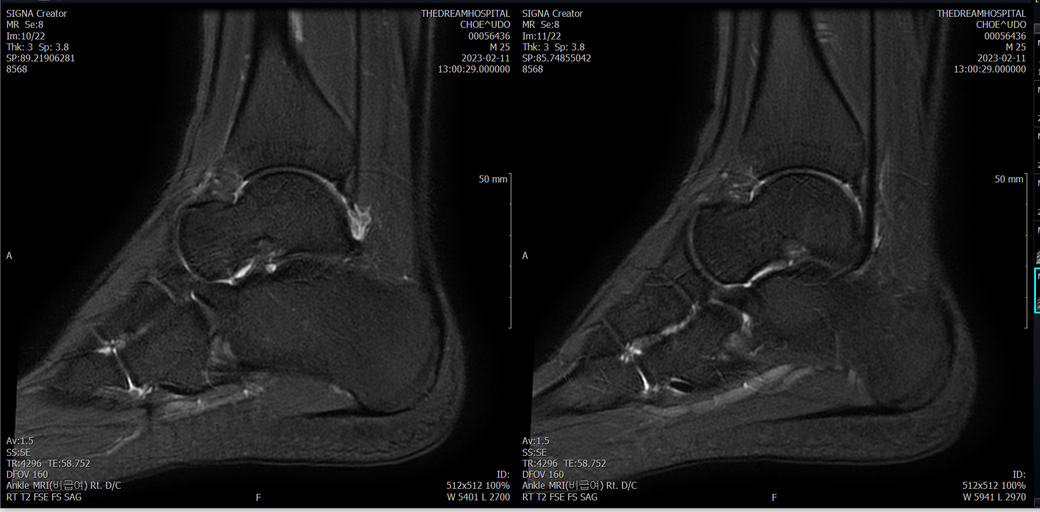

발목 mri 한번 봐주실수 있을까요?

오른발목 mri 전체사진입니다. 제가 병원을 갈수없는상황인지라.... 봐주시면 감사하겠습니다.

엑스레이에서는 문제가 없다고 하여 오른발목 mri촬영했습니다.

• 1번 째 사진

• 2번 째 사진